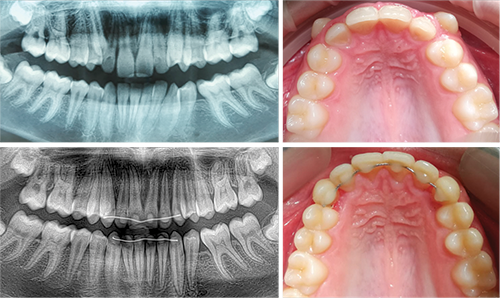

Before and after

Panoramic radiographs and maxillary occlusal views show the corrected orthoerupted position of the canines with root parallelism in 123 days (Fig. 10).

Fig. 10: Before and after; 123 days treatment time